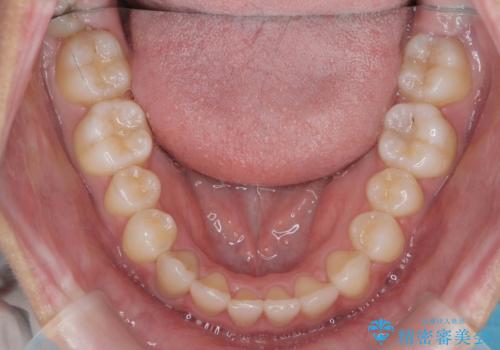

ガタつきの改善 マウスピース矯正治療

- 歯のがたつきの改善を求めて、矯正治療を希望され来院されました。

少量の歯のディスキング、歯列弓拡大、アタッチメントを装着することで審美的な歯列へとマウスピース矯正インビザラインを用いて治療を行います。

マウスピース矯正は装着時間の遵守が非常に大切ですが、しっかりと20時間/日以上の装着を守っていただいたおかげで良好な治療結果を得ることができました。